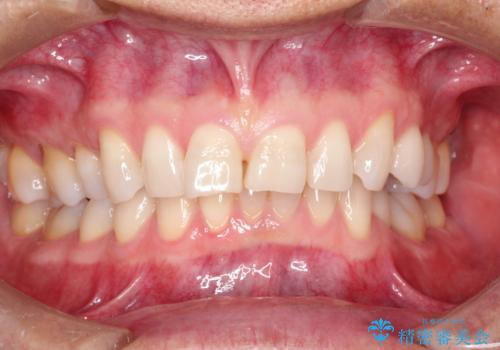

- 前歯のガタガタと前歯で食べ物が咬み切りにくいとのことで来院されました。

ガタガタの度合いが強く上下左右の前から4番目の歯を合計4本抜歯する計画としました。

また目立たない装置をご希望されたので、フルリンガルでの矯正治療となりました。

ガタガタの度合いが強く、上下の前歯が当たっていない状態であったので、治療期間が少し長くなりました。しかし、ガタガタがなくなり、前歯で食べ物が咬み切れるようになり、患者様にも満足していただけました。